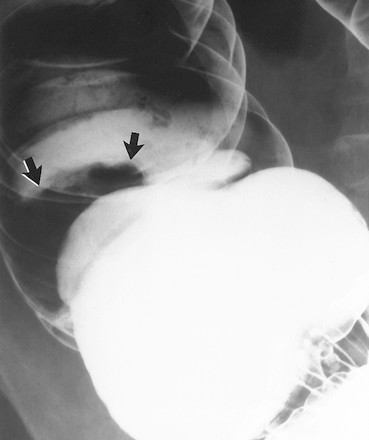

Ung thư biểu mô hình polyp thường thấy ở manh tràng hoặc trực tràng; có giả thuyết cho rằng do khẩu kính của các đoạn ấy to. Giống như các polyp đại tràng, các ung thư biểu mô hình polyp ở thành không đọng thuốc xuất hiện dưới dạng khuyết trong vũng baryt, trong khi các tổn thương ở thành không đọng thuốc là đường khắc màu trắng (Hình 13a, 13b). Để bộc lộ các khối u hình polyp khi chụp cản quang kép yêu cầu phải làm giãn quai ruột đầy đủ, đặt tư thế bệnh nhân đúng, và ép vũng baryt bằng tay một cách cẩn thận. Các khối hình polyp có thể bị bỏ sót nếu quai ruột không được làm căng đầy đủ (Hình 14).

Hình 13. Hình cản quang kép cho thấy khối ung thư biểu mô dạng polyp ở thành trước đại tràng. (a) Hình chụp nằm ngửa cho thấy khối dạng polyp được khắc bằng baryt (mũi tên) ở gần thành ngoài của đại tràng lên. (b) Hình chụp nằm sấp cho thấy hình khuyết nằm trong vũng baryt (mũi tên). Do đó tổn thương ở thành trước đại tràng.

Hình 14. Hình cản quang kép cho thấy ung thư biểu mô dạng polyp và tầm quan trọng của sự giãn căng. (a) Hình chụp khu trú, bệnh nhân nằm ngửa, đại tràng xuống không thấy tổn thương. (b) Hình chụp nằm ngửa, đại tràng căng hơn, bộc lộ rõ khối u hình polyp (mũi tên) không thấy ở hình a.